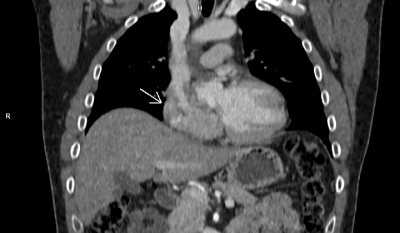

Jako vedlejší nález provedeného CT vyšetření byly popisovány defekty v kontrastní náplni pravé síně a okrsky kondenzace nejasné povahy v plicní tkáni. Na základě nálezu na CT byla indikována jícnová echokardiografie (TEE), kde byl identifikován keříčkovitý a částečně mobilní útvar v pravé síni (stěna celé pravé síně byla pokryta izoechogenními nástěnnými hmotami tloušťky 1,5–2 cm a pod Eustachovou chlopní z nich vycházel keříčkovitý velmi mobilní útvar délky až 5 cm) (obr. 2, video 1).

Dále jsme zjistili perzistující foramen ovale (PFO) s levopravým zkratovým prouděním. Následovalo PET/CT vyšetření, při kterém vykazovala tumorózní tkáň v pravé síni metabolickou aktivitu (obr. 3); naopak okrsky kondenzace v plicích aktivní nebyly.